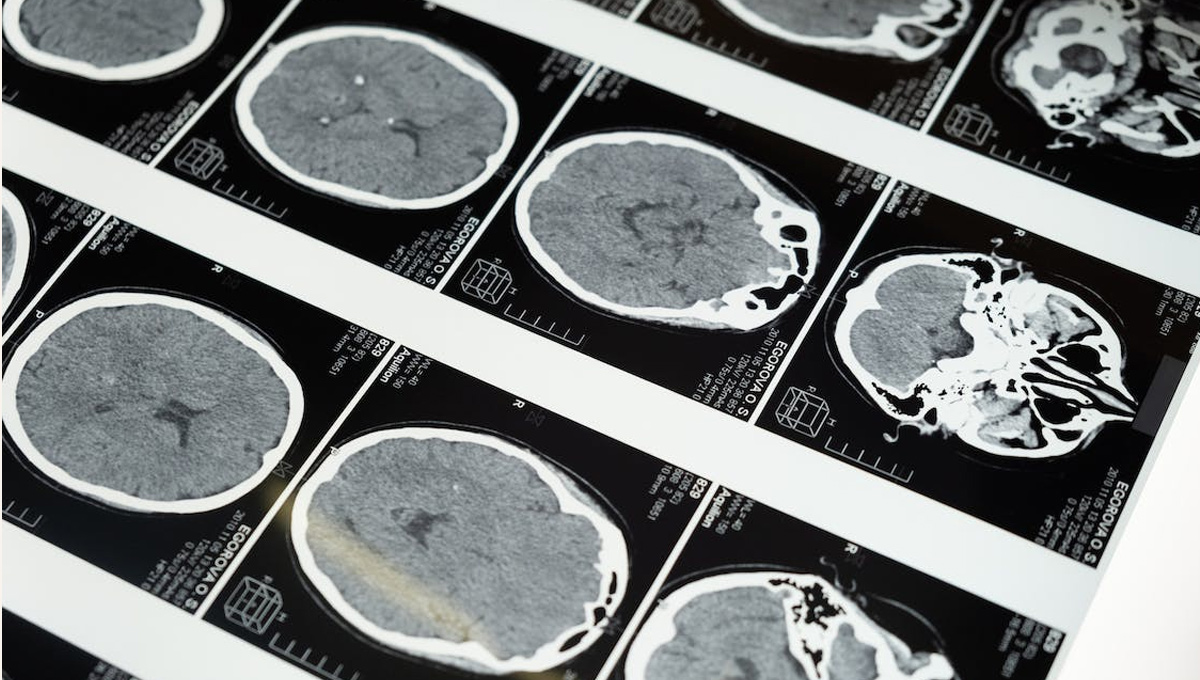

IIT Kanpur Research Unlocks Hope for Cancer Brain Disorders

भारतीय प्रौद्योगिकी संस्थान कानपुर (आईआईटी-के) ने बायोमेडिकल अनुसंधान में एक सफलता हासिल की है. जी प्रोटीन-युग्मित रिसेप्टर्स (जीपीसीआर) और केमोकाइन रिसेप्टर डी6 के अध्ययन के साथ, उन्होंने कैंसर और अल्जाइमर, पार्किंसन और स्किज़ोफ्रेनिया जैसे दिमाग के रोगों के इलाज के लिए नई संभावनाएं खोल दी हैं.

जी प्रोटीन-युग्मित रिसेप्टर्स (जीपीसीआर) मस्तिष्क की कोशिकाओं की सतह पर छोटे एंटेना की तरह होते हैं जो उन्हें संवाद करने में मदद करते हैं और कई मस्तिष्क कार्यों में महत्वपूर्ण भूमिका निभाते हैं. जब ये रिसेप्टर्स ठीक से काम नहीं करते हैं, तो मस्तिष्क की कोशिकाओं के बीच संचार में समस्याएं आती हैं, जिससे अल्जाइमर और पार्किंसन जैसे रोग होते हैं. इससे इन बीमारियों में देखे जाने वाले लक्षण और विकास होते हैं. इसी तरह, केमोकाइन रिसेप्टर D6 प्रतिरक्षा प्रणाली में काम करता है और सूजन की प्रतिक्रिया में शामिल होता है. कैंसर में, रिसेप्टर ट्यूमर के वातावरण को प्रभावित कर सकता है, जिससे कैंसर कोशिकाएं कैसे बढ़ती हैं और फैलती हैं.